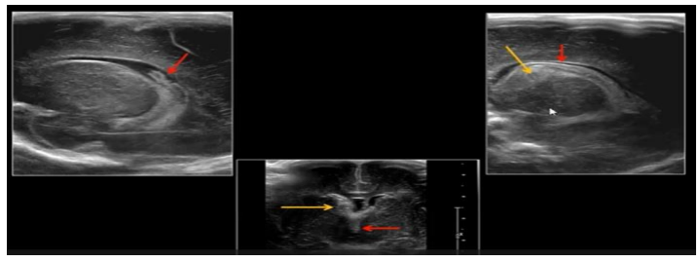

Masculino, com 4 semanas de vida, apresentando vômitos em jato não biliosos, principalmente

após as mamadas. Considerando a estenose hipertrófica do piloro a principal hipótese diagnóstica para

o caso descrito, os achados que esperamos encontrar no ultrassom EXCETO: